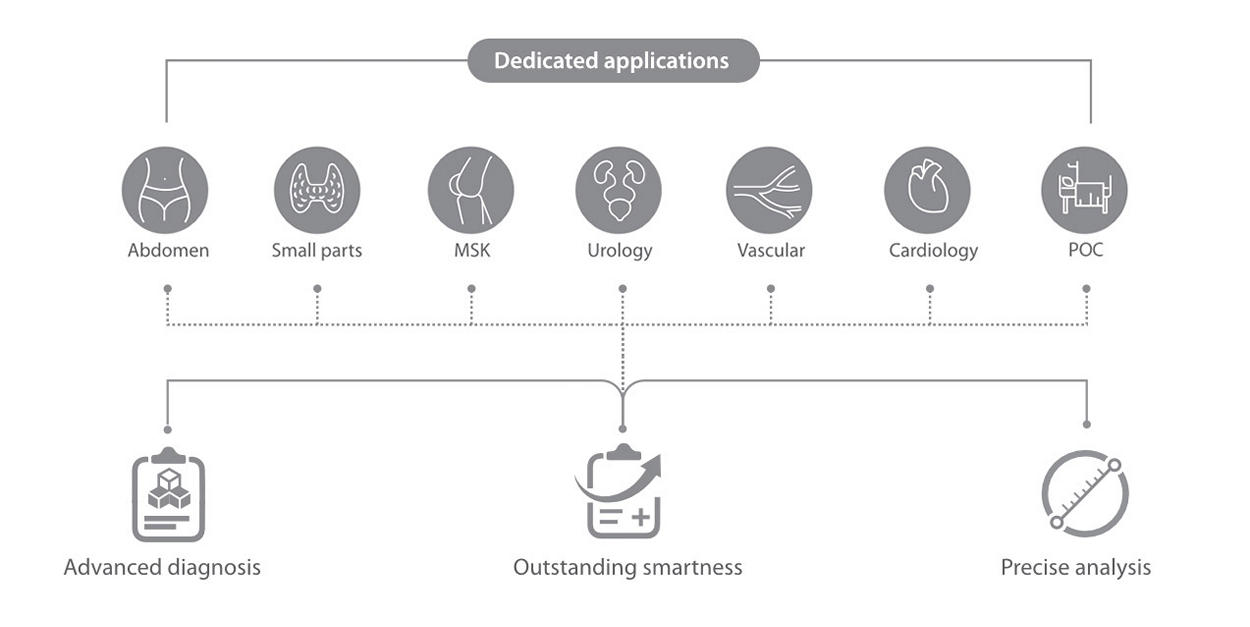

Resona I9 provides comprehensive clinical solutions for dedicated applications. Based on in-depth insights into different clinical scenarios, it delivers innovations that give users extreme clarity, outstanding intelligence and enhanced diagnostic confidence.